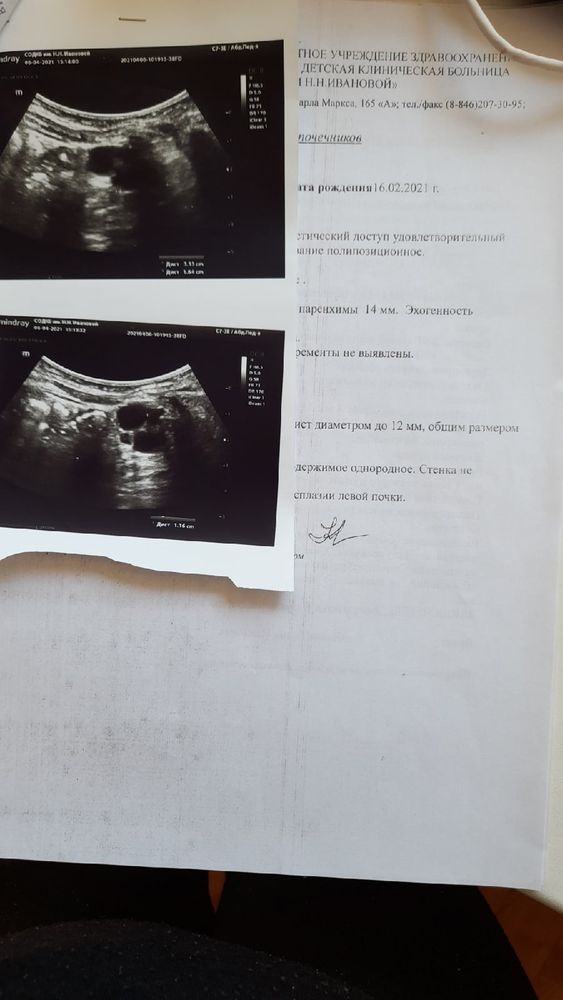

Хочу обратиться к вам за помощью! Совсем недавно я познакомилась с очень милой молодой девушкой у которой трое маленьких деток и один из них самый маленький болен неизлечимой генетической болезнью Муковисцидоз. Как это случилось думаю немногие знают, но встречала здесь на форуме подобные истории.... Вот история и результаты прикреплю ниже! При рождении ребёнка как всем известно в первые 3-4 дня жизни ребёнка берётся кровь из пяточки на 5 маркеров генетических заболеваний. Самая обычная процедура и все бы ничего если бы через несколько дней после выписки мамы и ребёнка из роддома и наслаждением материнства уже в стенах дома раздаётся звонок из генетического центра и сообщается о том что у вашего ребёнка превышен показатель крови на маркер в данной истории на муковисцидоз. А пока разговаривая с генетиком по телефону ты впервые слышишь об этом заболевании но понимаешь что есть какие то отклонения! Тебя просят пересдать кровь ребёнку! Ты вешаешь трубку и лезешь в интернет читать что же это за заболевание такое. И вот тут прочитав об этом смертельном и неизлечимом заболевании и глядя на своего спящего любимого комочка думаешь только об одном- почему именно тебя это коснулось и твоего ребёнка, за что, почему, и только бы все это оказалось неправдой! Затем процедура подтверждения следующая! Нужно пересдать кровь в определенные дни жизни ребёнка и если показатели крови опять же превышают дальше нужно ещё одно подтверждение или отрицание это сдавать анализ на потовые пробы.